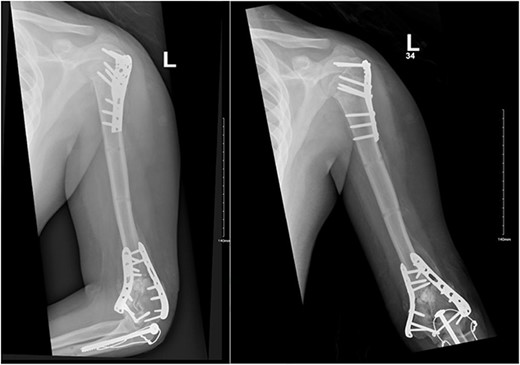

After surgery, the patient was taken back to the ICU and was followed daily by the upper limb orthopedic surgery team for wound care and change of dressings. Four days later, the patient’s condition had improved and he was assessed for distal neurovascular function, which was intact. Afterwards, range of motion was assessed, and no complications were reported before discharge. The patient was kept as an inpatient for almost two more months under the orthopedic trauma team for continuation of management and patient optimization. After discharge, the patient was followed in the orthopedics upper limb and trauma clinic for almost 3 years (Figs 4– 6).

(A). Late follow-up anteroposterior (AP) view of the left elbow after ORIF. (B) Late follow-up lateral view of the left elbow after ORIF.

(A) Late follow-up anteroposterior (AP) view of the left shoulder after ORIF. (B) Late follow-up lateral scapula (Y- view) view of the left shoulder after ORIF.

(A) Late follow-up internal oblique view of the left elbow after ORIF. (B) Late follow-up external oblique view of the left elbow after ORIF.

Our patient was followed afterwards for three years with serial x-rays. No signs of growth arrest or deformity due to our surgical intervention were noted. Instead, on follow up, our patient had a functional range of motion. Elbow range of motion was documented to be 30° extension to almost full flexion and intact pronation and supination. The range of shoulder motion was documented as full. Good healing was observed, but there was some hardware prominence that slightly affected the range of motion, and the patient will be booked for hardware removal. The patient was happy and satisfied about the overall outcome and restored functionality.